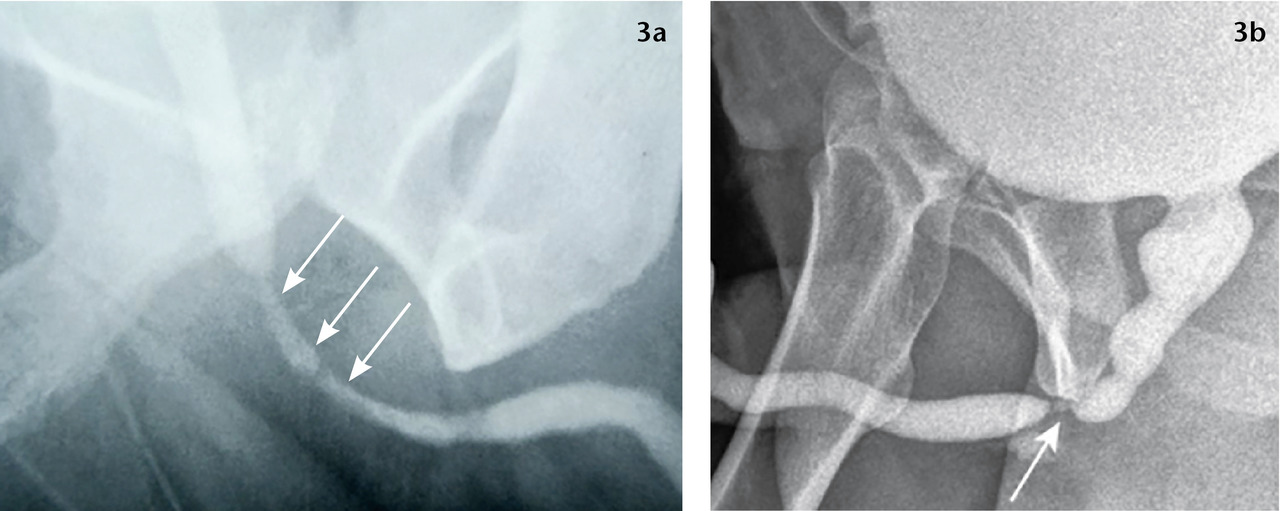

L’urétrocystographie rétrograde et permictionnelle (UCRM), indispensable, précise la localisation, la longueur et le nombre de sténoses. Opacification rétrograde de l’urètre et de la vessie par injection de produit de contraste au méat urétral, elle comprend une première série de clichés statiques et une seconde durant la vidange vésicale (fig. 2 et 3).2